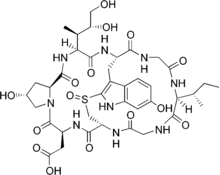

The species is now known to contain two main groups of toxins, both multicyclic (ring-shaped) peptides, spread throughout the mushroom tissue: the amatoxins and the phallotoxins. Another toxin is phallolysin, which has shown some hemolytic (red blood cell–destroying) activity in vitro. An unrelated compound, antamanide, has also been isolated.

Amatoxins consist of at least eight compounds with a similar structure, that of eight amino-acid rings; they were isolated in 1941 by Heinrich O. Wieland and Rudolf Hallermayer of the University of Munich.[32] Of the amatoxins, α-amanitin is the chief component and along with β-amanitin is likely responsible for the toxic effects.[57][58] Their major toxic mechanism is the inhibition of RNA polymerase II, a vital enzyme in the synthesis of messenger RNA (mRNA), microRNA, and small nuclear RNA (snRNA). Without mRNA, essential protein synthesis and hence cell metabolism grind to a halt and the cell dies.[59] The liver is the principal organ affected, as it is the organ which is first encountered after absorption in the gastrointestinal tract, though other organs, especially the kidneys, are susceptible.[60] The RNA polymerase of Amanita phalloides is insensitive to the effects of amatoxins, so the mushroom does not poison itself.[61]

The phallotoxins consist of at least seven compounds, all of which have seven similar peptide rings. Phalloidin was isolated in 1937 by Feodor Lynen, Heinrich Wieland's student and son-in-law, and Ulrich Wieland of the University of Munich. Though phallotoxins are highly toxic to liver cells,[62] they have since been found to add little to the death cap's toxicity, as they are not absorbed through the gut.[59] Furthermore, phalloidin is also found in the edible (and sought-after) Blusher (Amanita rubescens).[32] Another group of minor active peptides are the virotoxins, which consist of six similar monocyclic heptapeptides.[63] Like the phallotoxins, they do not induce any acute toxicity after ingestion in humans.[59]